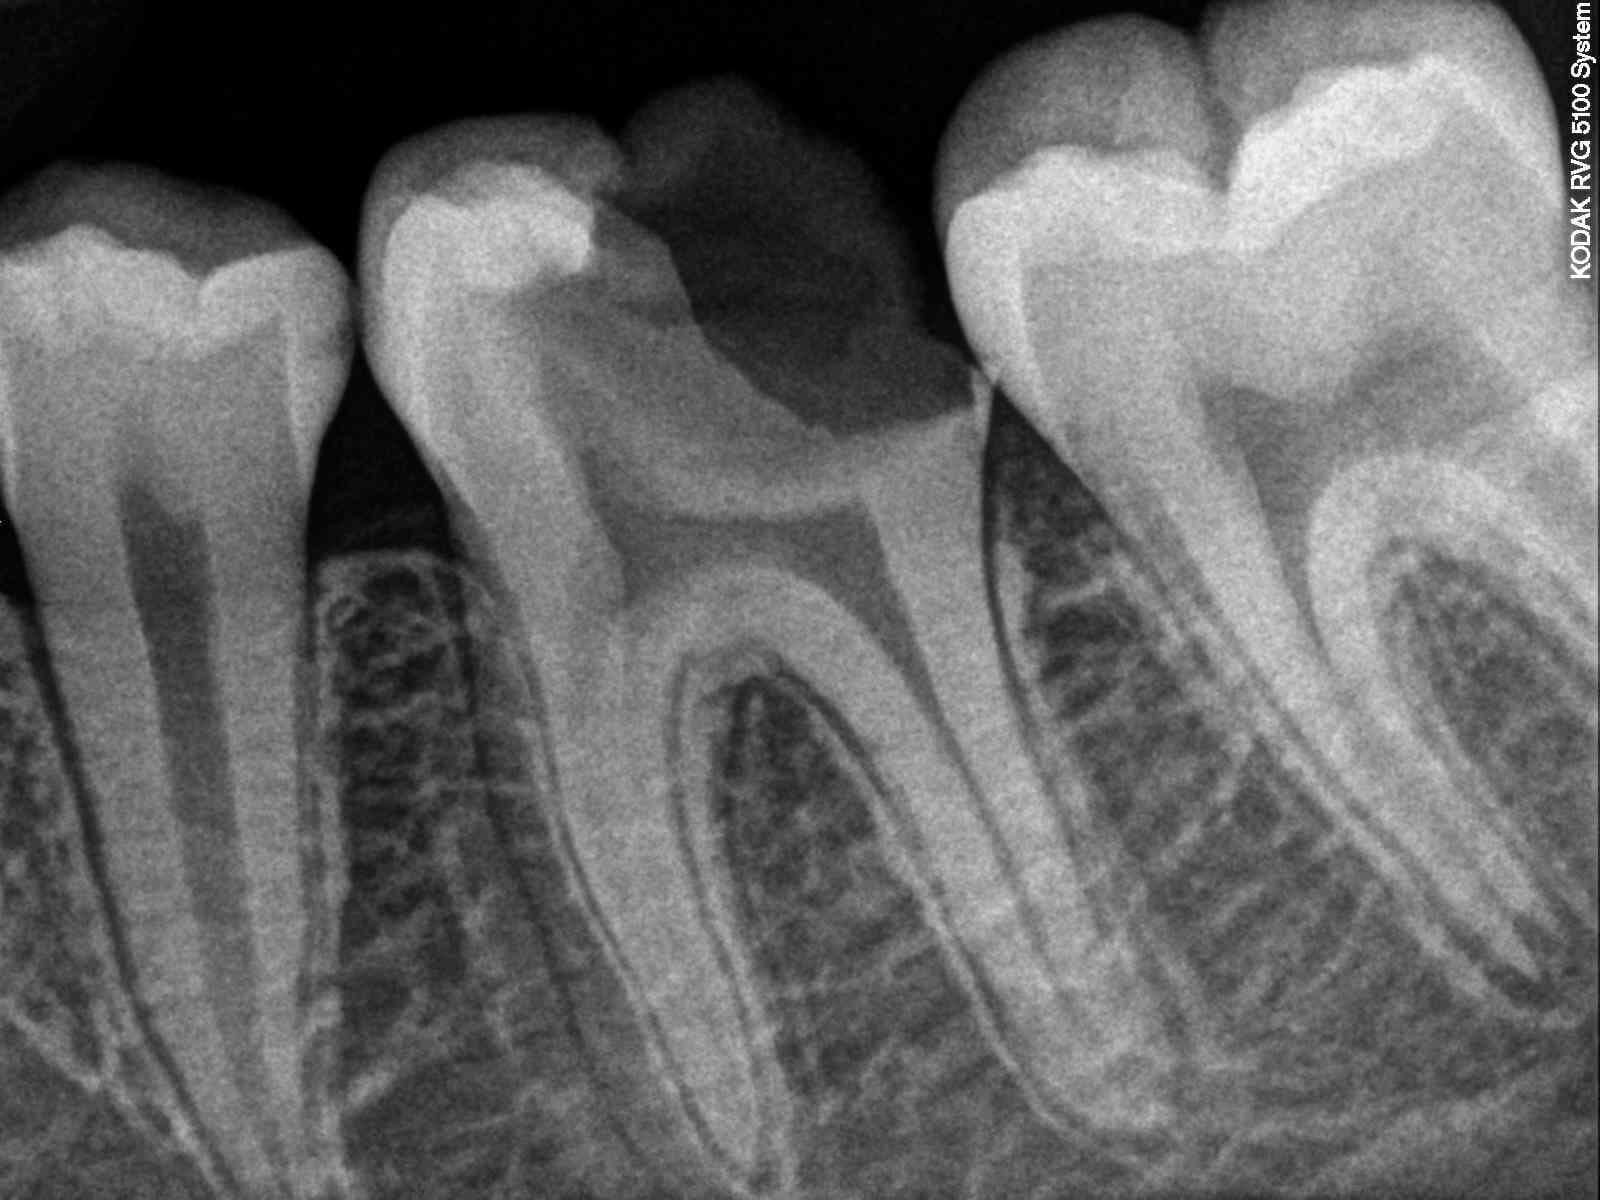

Extraction de la 6 ( en deux temps si possible) et fermeture de l'espace

L’extraction de la 46 tu la fait quand l'ortho te dit que le premier semestre est réglé.

Oui, cela fonctionne dans la cadre de la CMu, mais aujourd'hui comme le rappelle lardon c'est l'extraction d'une dent qui peut être conservée autrement.

Une extraction en deux temps c'est quand tu extrais une racine ferme l'espace et extrait la deuxième. Ca te permet de conserver le volume osseux et d'augmenter ou de réduire l'ancrage suivant la racine choisie.

Là une 6 a extraire et l'on veut augmenter l'ancrage, donc on extrait la racine mesial.